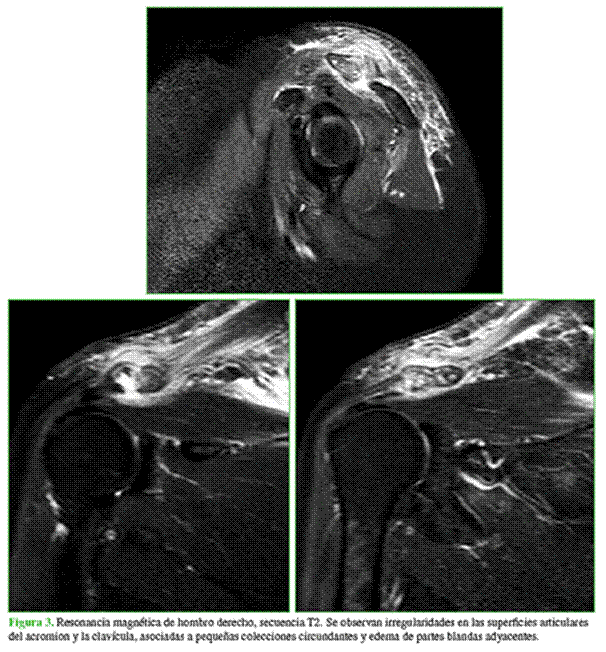

Solicitamos radiografías de hombro derecho de frente y axial escapular (Figura 2), en las que se observó radiopacidad en la región supracromial, y también una resonancia magnética que reveló irregularidades en las superficies articulares tanto del acromion como de la clavícula, asociadas a pequeñas colecciones circundantes y edema de partes blandas adyacentes (Figura 3).